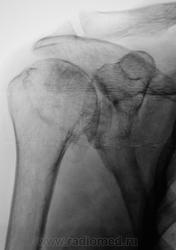

Жалобы на длительные боли в плечевом суставе

Таков артроз.

Смущает дополнительный "контур" по стрелкам.

Думаю,что это "неодокостеневшие" костные разрастания(не знаю,как точно обозвать).

ДОА.

Что в анамнезе? Была травма? После чего боли появились. Что можно сказать об объёме движений? Мне кажется, что изменения связаны с обызвествлением суставной сумки.

Боли в течение последних двух - трёх лет. Четко (при разговоре) травму вспомнить не может, хотя жительница сельской местности, где травмой считается, ну минимум перелом.

Мне кажется, что изменения связаны с обызвествлением суставной сумки.

Мне тоже так показалось.